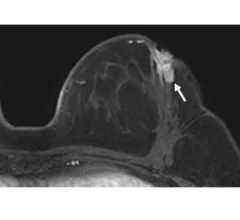

Magnetic resonance imaging of the breast (breast MRI), commonly used for dense breasts, is a highly accurate imaging modality for detecting early breast cancer and other abnormalities without using excess radiation. It’s often used alongside digital mammograms and digital breast tomosynthesis to offer detailed visualization of breast lesion margins.